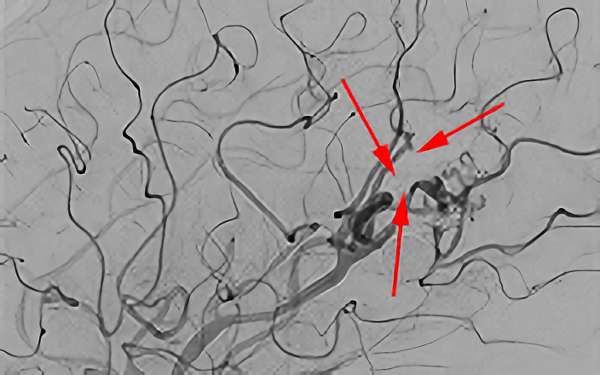

No.1620 手術前

No.1620 手術中

No.1620 手術後